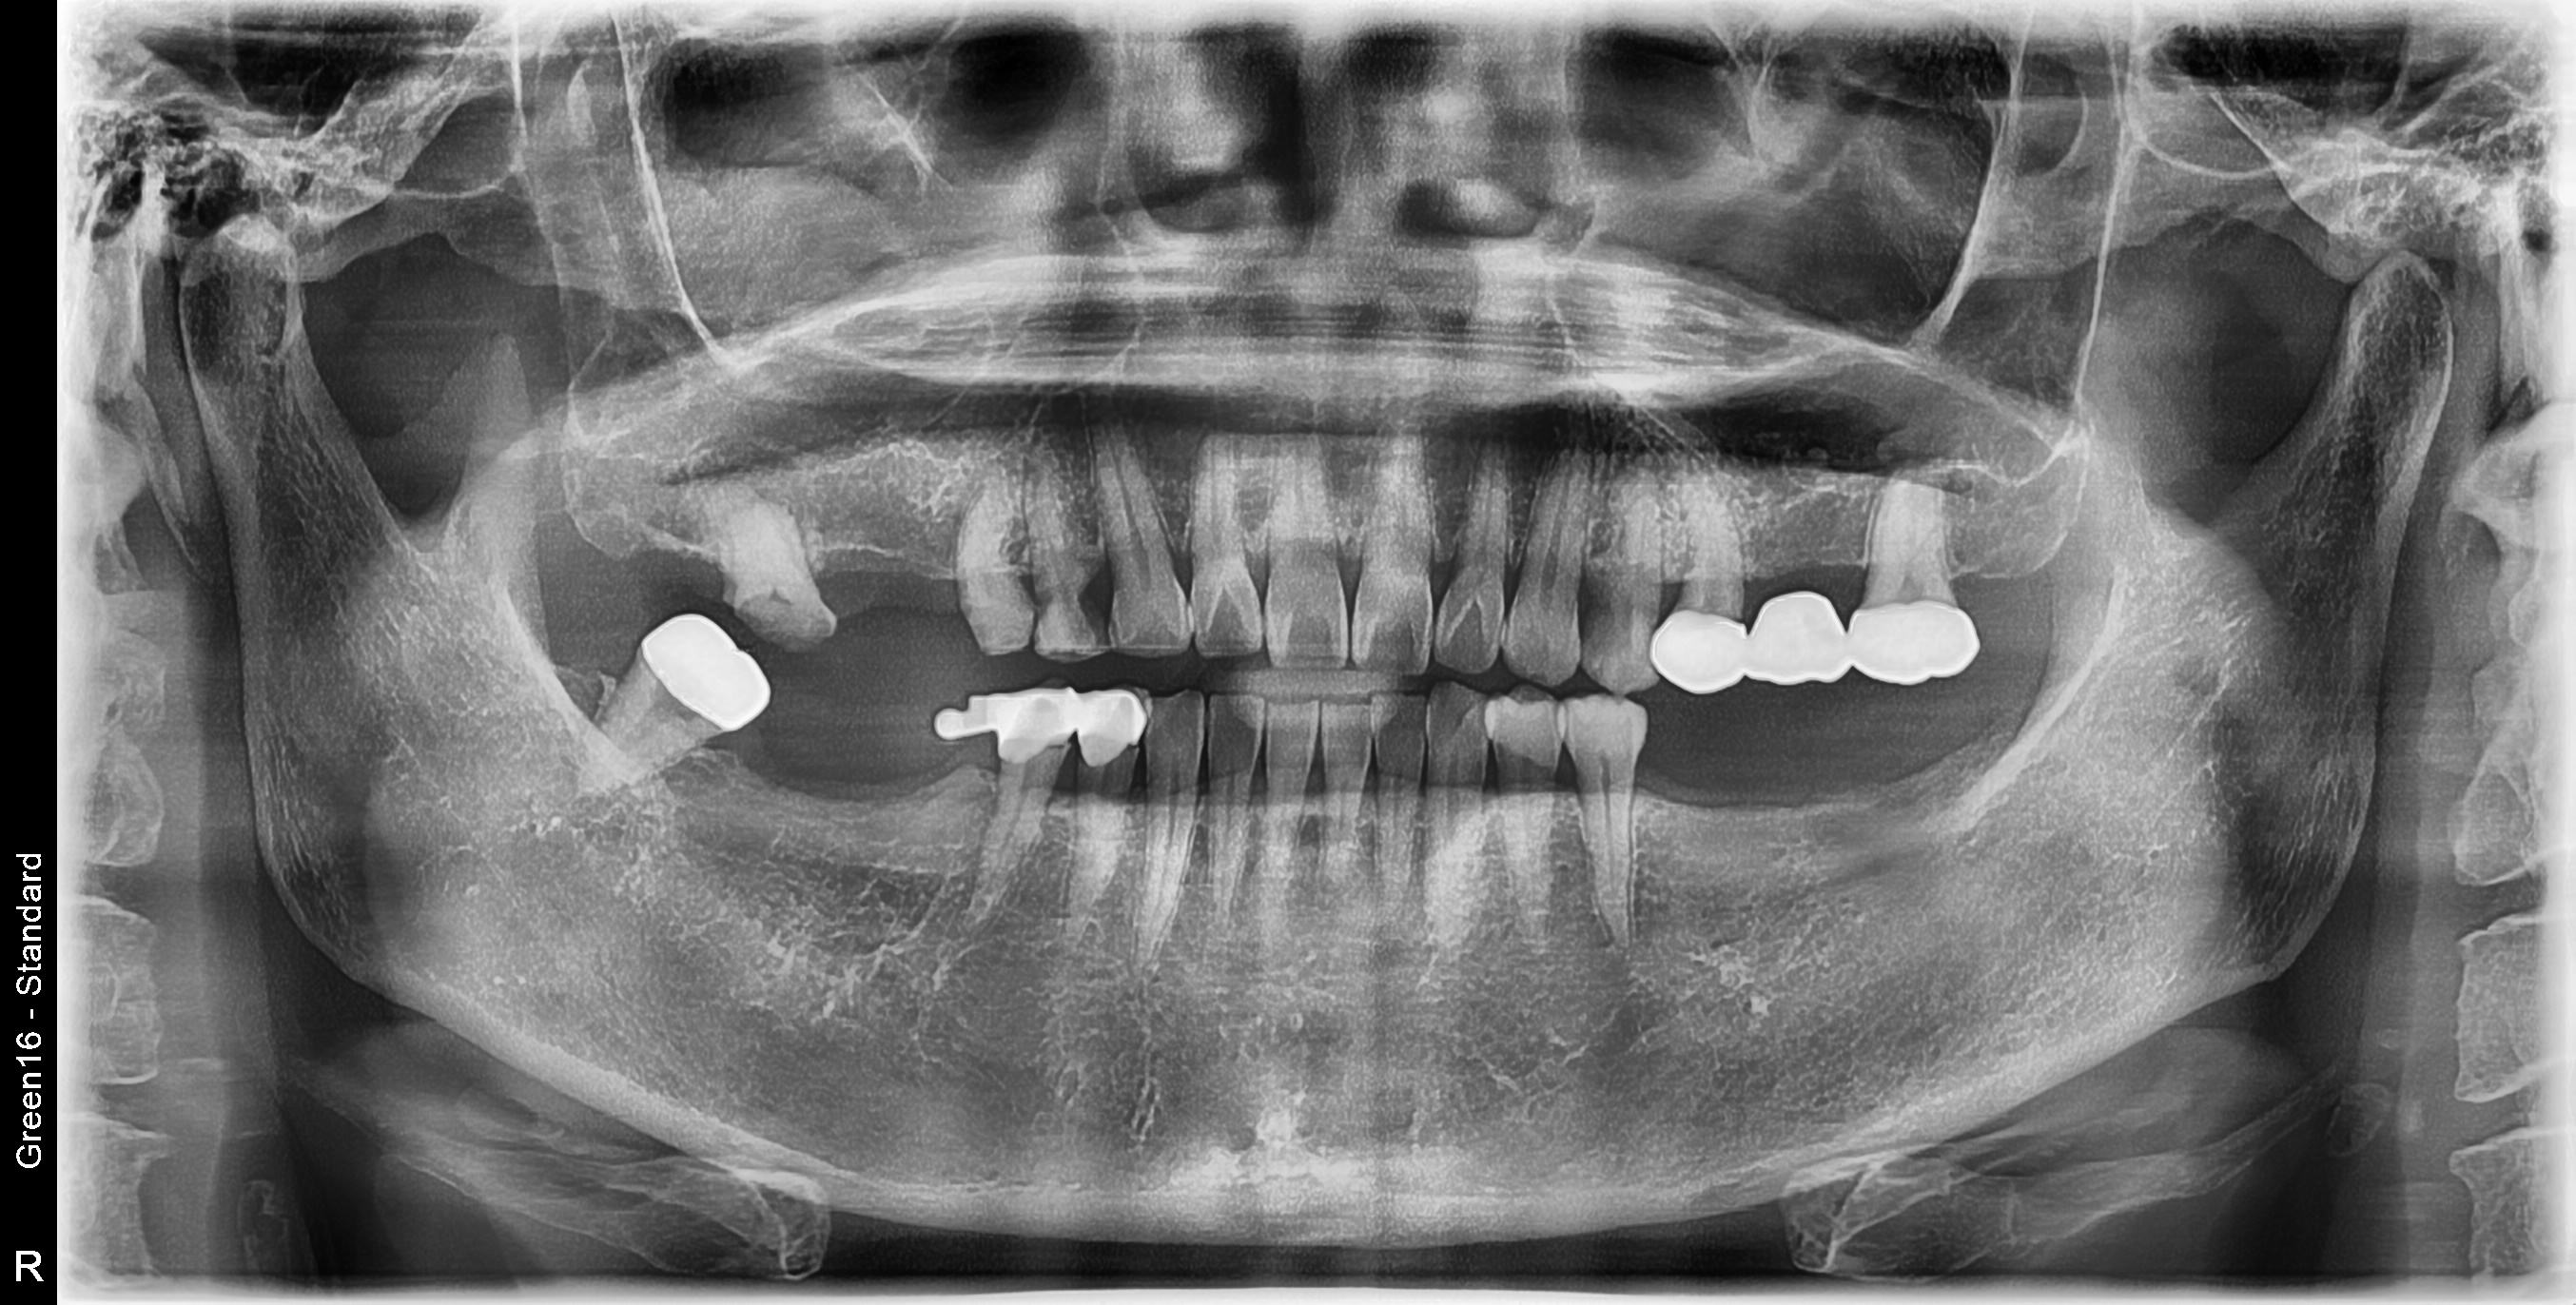

우측 매복사랑니 발치 난케이스 사례

전후사진

수술 전

수술 후